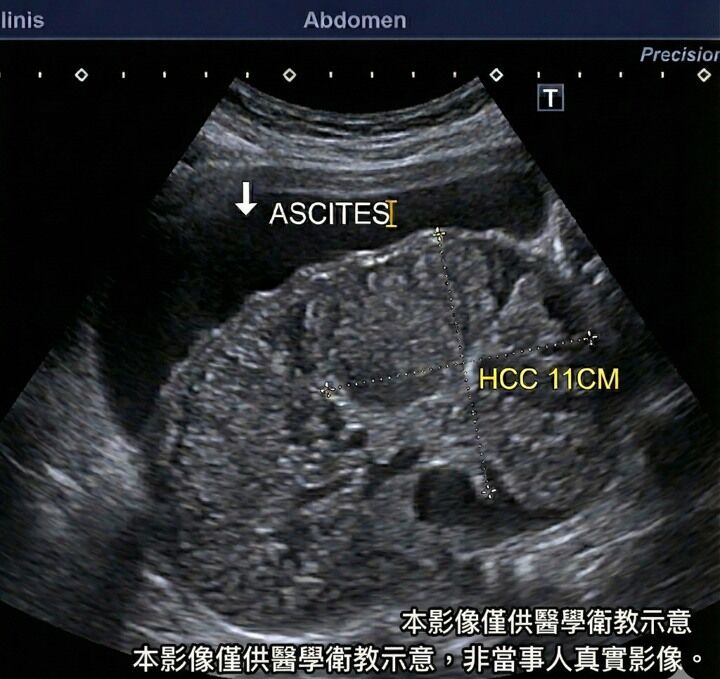

▲男子不只被檢查出患有肝硬化,還有顆11公分的巨大肝腫瘤。(示意圖/非當事人影像/卓韋儒醫師提供)

腸胃不適別輕忽!一名40歲男子因腹脹求診,原以為只是脹氣、拿點藥就好,但醫師卓韋儒一見到他「臉色不對、肚子大得不自然」,心中警鈴瞬間大響。緊急掃超音波後,竟驚見滿肚子腹水,影像顯示為嚴重肝硬化,還有一顆11公分的巨大肝腫瘤,確診罹患肝癌。病情遠超預期,讓診間氣氛瞬間凝重。

雲林長庚醫院肝膽胃腸科主治醫師卓韋儒接受《ETtoday健康雲》採訪時還原當時狀況,男子求診時膚色灰暗,因黃疸影響,皮膚呈現土黃色且乾澀無光,眼白也明顯偏黃。此外,他凸起的肚子與一般的「啤酒肚」不同,這種「病理性腹脹」摸起來異常堅硬、緊繃,皮膚甚至被撐到發亮。若平躺敲擊腹部兩側,會出現明顯的濁音,一旦改變姿勢,聲音位置會隨水流移動,這就是典型的腹水徵兆。

針對該名患者腫瘤已達11公分,卓韋儒表示,現階段目標為優先縮小腫瘤,爭取後續手術切除或電燒的機會。他強調,雖然治療難度高,但「並非絕路」。過去晚期肝癌存活期可能不到半年,但受惠於免疫療法聯合標靶治療的進步,如今許多患者能有效控制病情,不僅存活期可延長至2年甚至更久,也能維持不錯的生活品質。